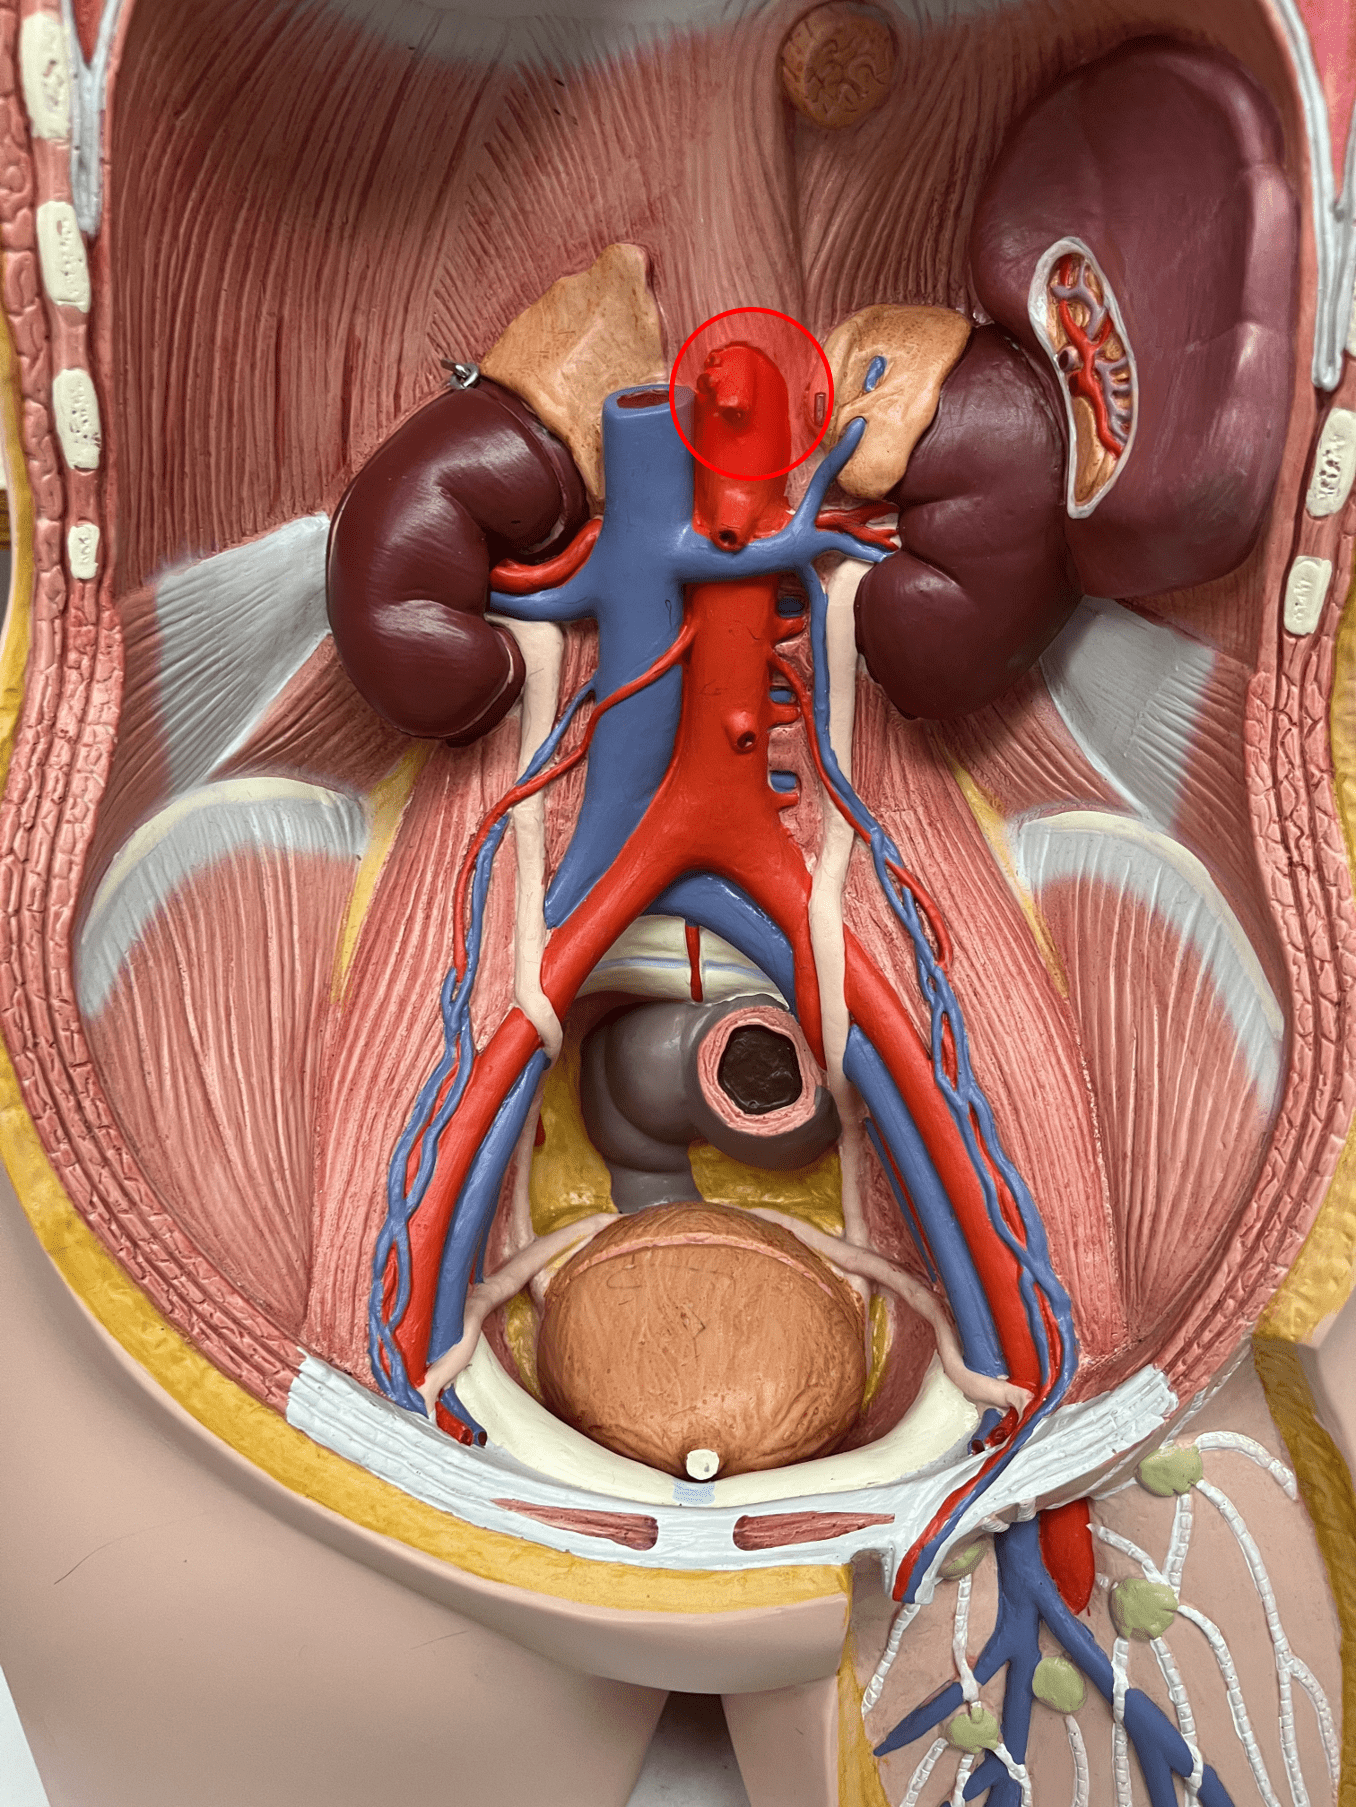

tunica externa

• Composed of loose connective tissue and collagen fibers.

• Also known as the tunica adventitia.

7

New cards

external elastic membrane

• A thin layer of elastic connective tissue.

• Found between the tunica externa and tunica media.

• Found between the tunica externa and tunica media.